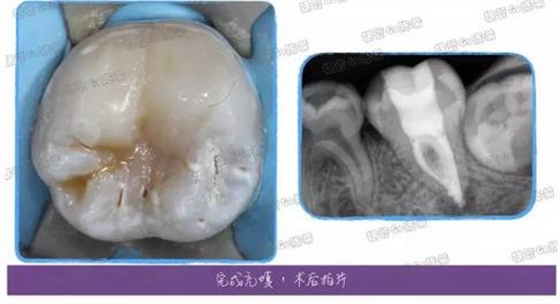

兩周復(fù)診后,疼痛消除,無其他癥狀,就使用AH根充糊劑+0430及修整后的0625牙膠尖配合熱牙膠充填了,充填完以后覺得這個(gè)C型很明顯,又用內(nèi)窺鏡拍了一下。

完成樹脂充填后,右邊那條頭發(fā)絲樣的東西最開始以為是電腦屏幕有頭發(fā),擦了半天沒擦掉,估計(jì)是反光板拍照時(shí)落下的了。樹脂的塑形一直做得不好,這例算是稍微好點(diǎn)的了,所以拿出來請(qǐng)大家指教指教~

2017年的目標(biāo)之一就是提高修復(fù)方面的技藝啊~

堆塑完成后再拍個(gè)根尖片檢查檢查~